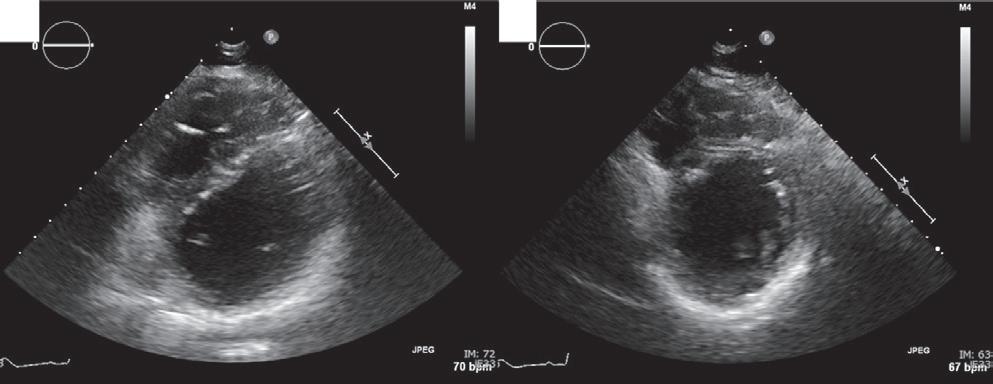

A 57-year-old man presented with a three-decade history of recurrent episodes of palpitation with alarming jugular venous pulsation, but without syncope. Each episode spontaneously reverted to the normal sinus rhythm 6–8 hours after the onset. Cardiac auscultation raised the suspicion of underlying rheumatic mitral stenosis. A 12-lead ECG was suggestive of a WPW pattern with a right posterior septal accessory pathway (Figure 1A). A chest X-ray in the posterior–anterior view was consistent with cardiac auscultation (Figure 1B). A transoesophageal echocardiogram confirmed rheumatic mitral stenosis (Figure 2A and Supplementary Material Video 1). The pliable mitral valve area was 0.8 cm2 and the mean gradient was 17 mmHg at a heart rate of 87 BPM. The coronary angiogram was normal.

On the day of the procedure, the first balloon mitral valvotomy was performed from a right femoral approach using a 23–26 mm Accura balloon (Vascular Concepts) after transeptal access using an 8 Fr SL-1 sheath and a BRK-0 needle (St Jude Medical). A transeptal puncture was performed after proper needle tip position was confirmed by fluoroscopy (right anterior oblique, left anterior oblique and 90° lateral views) and transoesophageal echocardiography (bicaval and short axis views; Figure 3A). The mean left atrial pressure prior to the valvotomy was 31 mmHg. The balloon was inflated to 26 mm in the right anterior oblique 20° position under fluoroscopy (Figure 3B) because the patient was 160 cm tall. The mitral valve area increased to 2.2 cm2 without any additional mitral regurgitation, and the mean left atrial pressure decreased to 12 mmHg without any mitral valve gradient. Immediate transthoracic echocardiography showed that the mitral valve gradient had decreased to 7/2 mmHg with negligible mitral regurgitation.